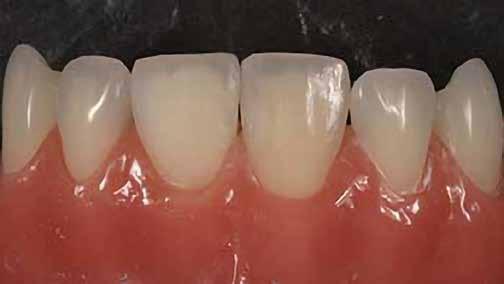

A fogászati kezelések során manapság már nem kizárólag az esztétikai megjelenés helyreállítására törekszünk. Sokszor a kedvezőtlen esztétikai megjelenés hátterében álló okok következményes módon a fogazat funkcionális működését is károsítják, így a kezelések során ezeknek a helyreállításával is foglalkoznunk kell. A különböző funkcionális és esztétikai diszkrepanciák kezelésére számtalan módszer létezik, ám ezen fogászati beavatkozások mindegyikében közös, hogy a kivitelezésük során nagyon szoros együttműködésre van szükség a kezelést végző fogorvos és a munkáját segítő fogtechnikus között. Az alábbi esetbemutatás során egy fiatal hölgypáciens fogazatának héjak alkalmazásával történő esztétikai és funkcionális rehabilitációját szeretnénk ismertetni.

A 19 éves hölgypáciens azzal a kéréssel jelentkezett a rendelőnkbe, hogy szebb fogakat szeretne. Az első konzultáció alkalmával megkérdeztük, hogy mi zavarja leginkább a fogazatának jelenlegi megjelenésében, valamint azt is megbeszéltük vele, hogy milyen végeredmény elérése esetén lenne maradéktalanul elégedett. Ebben az esetben a kezelési célokat az alábbiakban határoztuk meg:

A páciens fogazata esztétikai megjelenésének és funkcionális működésének a lehető legtöbb, saját foganyag megtartása mellett történő helyreállítása (1. és 3. ábra).

A lehető legideálisabb esztétikai végeredmény elérése érdekében néhány esetben a fogak alakjának módosítá -

A kezelés megtervezése során kifejezett jelentősége van annak, hogy jó kommunikáció legyen a páciens, a fogorvos és a fogtechnikus között. A páciens leendő fogazatának természetes megjelenését a kezelésben részt vevő team szakmai felkészültsége, gyakorlati tapasztalata és a kezelés sikerességének irányába történő elkötelezettsége biztosítja. A beavatkozások megkezdése előtt megtörtént a páciens anamnézisének a felvétele, valamint a klinikai kivizsgálását is elvégeztük. Ezt követően lenyomatokat készítettünk a kiindulási állapotról, majd a kiindulási helyzetet extra- és intraorális fotók segítségével is rögzítettük (13. a-c. ábra).

A kezeléstervezés egyik legfontosabb lépése a mock-up elkészítése. A mock-up alapjául szolgáló wax-up-ot (felviaszolás) is ugyanolyan részletességgel kell a fogtechnikusnak elkészíteni, mintha azok már a végleges fogpótlások alapjául szolgáló mintázatok lennének. A mock-upnak nagyon pontosan kell illeszkednie, valamint a tervezett fogpótlás meg-

jelenését is rendkívül élethűen kell reprezentálnia. Ahhoz, hogy a páciens mock-uppal kapcsolatos első benyomásai kedvezőek legyenek, a mock-up színének a páciens „szemfehérjének” színével meg kell egyeznie. A kezelési cél páciens által történő elfogadása és a tervezett eredménnyel kapcsolatos „wow-effektus” kialakulása nagyban függ a páciensben az első megtekintés során kialakult első benyomásoktól.

Az eddigi tapasztalataink szerint a páciensek jelentős többsége egyértelműen kifejezi az elégedettségét, ha a mock-up megfelel az eredeti elképzeléseiknek. A bemutatásra kerülő esetben is ez történt. A tervezett végeredmény megtekintését követően a páciens azonnal kérte az általunk javasolt kezelési tervben ismertetett beavatkozások elvégzését. A héjak alapanyagául az Ivoclar Vivadent által gyártott A1-es színű Telio CS kerámiát javasoltuk. Az anyagválasztás hátterében az állt, hogy ez az anyag nagy keménységgel rendelkezik, valamint az, hogy a felszínét nagy simaságúra lehet polírozni. A páciens rendkívül fiatal életkora is azt a terápiás koncepciót erősítette, hogy a kezelés során lehetőség szerint kizárólag non-invazív beavatkozásokat alkalmazzunk.

A különböző kezelési lehetőségek ismertetése során három eltérő terápiás megoldást vázoltunk fel számára:

• Állcsont-orthopédiai kezelés;

• Kompozittal történő direkt felépítés;

• Non-prep és minimál invazív előkészítést igénylő héjakkal történő ellátás.

A különböző terápiás lehetőségek bemutatása során a kezelésekkel járó lehetséges előnyök és hátrányok is ismertetésre kerültek.

A páciens már kezdetben is rendkívüli érdeklődést mutatott a preparálást nem igénylő (non-prep), héjakkal történő ellátással kapcsolatban. Ennek a terápiás modalitásnak az előnyei közé tartozik, hogy a fogakat egyáltalán nem, vagy csak minimál invazív módon kell preparálni, nincs szükség ideiglenes héjak készítésére, a héjak alapanyagául szolgáló kerámia nem hajlamos az elszíneződésre, nem jellemző a beavatkozások elvégzését követően jelentkező posztoperatív szenzitivitás, valamint hogy ezzel a módszerrel rendkívül kedvező esztétikai végeredményt lehet elérni. A fenti előnyök rendkívül meggyőzően hatottak a páciensre. A döntése során azt is figyelembe vette, hogy amennyiben ezeket a viszonylag költséges restaurátumokat választja, akkor ez a kezelés végösszegét is jelentős mértékben befolyásolja.

A kezelés során az jelentette a legnagyobb kihívást, hogy a héjakkal ellátott fogak élethűen utánozzák a természetes fogazat megjelenését. A fogpótlás színének, valamint a restaurátumok felszíni textúrájának és alakjának harmonikusan kell a páciens arcesztétikájához és karakteréhez illeszkednie.

A tényleges protetikai ellátás megkezdése előtt a páciens mosolygás közben látható fogait otthoni fogfehérítés keretei között a kérésének megfelelő A1-es fogszín eléréséig fehérítettük. A fehérítés során a későbbiekben héjakkal ellátásra kerülő fogak színén nem változtattunk. A fogak előkészítése részeként csupán a két felső nagymetsző (1.1,2.1) incizális élét kellett kismértékben redukálni. A többi felső front fog (1.3,1.2,2.2,2.3) nem került preparálásra.

A platinafólia technikát 1896 óta alkalmazzák. Napjainkra az eredeti eljárás már kismértékben módosításra került, de lényegében ugyanazzal a módszerrel történik a platinafóliára készülő koronák és héjak elkészítése. A minimál invazív fogászat egyre szélesebb körben történő elterjedésének köszönhetően ez az eljárás a reneszánszát éli. A pácienseink egyre gyakrabban szeretnék a fogaik alaki, színi vagy helyzeti rendellenességeit a lehető legkisebb saját foganyagveszteség árán korrigáltatni. Az eljárás során 0,025 mm vastag 99,9%-os tisztaságú platinafólia kerül alkalmazásra. Amennyiben a megfelelő technikai háttér és a beavatkozások elvégzéséhez szükséges elméleti és gyakorlati szaktudás is rendelkezésünkre áll, akkor semmi sem állhat az utunkba a pácienseink új mosolyának kialakítása során.

A módszer első lépéseként a gipszből kiöntött csonkokat platinafóliával borítjuk (5. ábra). Az adaptálását követően a felhelyezett fóliát óvatosan eltávolítjuk, felhevítjük, majd ismét visszahelyezzük a csonkokra. Ezt követően történik meg az első kerámiaréteg felvitele (Waschbrand). Az első égetés során csupán egy nagyon vékony réteg kerámia kerül a fólia felszínére (6. ábra). Amikor az égetést követően ezt

a kezdetleges kerámiavázat visszahelyezzük a csonkokra, a kerámia anyagában vékony repedések alakulnak ki. A végleges restaurátum elkészítéséhez szükséges kerámia „köpeny” ekkor áll készen a további kerámiarétegek felvitelére és kiégetésére (opaker réteg, dentin- és zománcmassza felvitele) (7-10. ábra). A készülő fogpótlás végső formai megjelenése rétegenként kerül kialakításra.

A második égetés során szintén csupán egy nagyon vékony réteg transzlucens opalmassza kerül felhelyezésre. A restaurátum formai megjelenésének és a felszíni textúrák kialakítására csak ezt követően kerül sor. A fényégetés során nem alkalmazunk glazúrmasszát. A készre vitel során elérni kívánt, magas fényű polírt kézi eszközök alkalmazásával alakítjuk ki. A restaurátumok végső kidolgozását követően a platinafóliát egy csipesz segítségével óvatosan eltávolítjuk, majd a kifejezetten vékony héjakat a kontroll mintára helyezzük. Ezt követően a pótlások megfelelő illeszkedésén kívül a funkcionális elmozdulások közben kialakuló érintkezéseket és a kontaktpontokat is ellenőrizzük. Az ilyenkor esetlegesen szükségessé váló korrekciók elvégzésére a Ducera® LFC (Dentsply Sirona) kerámiaanyagot használjuk. A kész munka fogorvosi rendelőbe való szállítása előtt kifejezett jelentőséggel bír az elkészült restaurátumok gondos becsomagolása. Az átadni kívánt fogpótlások sérülésmentes szállíthatóságának biztosítása elengedhetetlen az eddigi munkánk védelme szempontjából.

A héjak átadását követően kialakuló állapot valósághű módon történő bemutatása érdekében próbapasztát alkalmaztunk (Try-In-Paste; Variolink® Esthetik Try-In-Paste, Ivoclar Vivadent) (11. ábra). A próba során ellenőrizzük a héjak színét, formáját és transzparenciáját. A próbapaszta alkalmazásának egyik lényeges pontja, hogy a paszta színe egyezzen meg a végleges beragasztás során alkalmazni kíván ragasztóanyag színével. A héjak végleges rögzítése során mindig adhezív rendszereket használunk.

A preparálást nem igénylő héjak általában nagyon vékonyak, és sajnálatos módon ebből adódóan a végleges átadásuk előtt történő előkészítés során könnyen eltörhetnek. Csupán a páciensek saját fogain történő végleges rögzítés révén kapják meg azt az alátámasztottságot, amely a végleges töréssel szembeni ellenálló képességüket biztosítja. A fogpróba során a héjakat egyesével a fogakra helyezzük, és ellenőrizzük a pontos illeszkedésüket, valamint az approximális kontaktpontok megfelelőségét. Amenynyiben mindent rendben találtunk, úgy hozzákezdhetünk a héjak adhezív módszerrel történő rögzítéséhez szükséges előkészületek elvégzéséhez. Első lépésként a héjak elhorgonyzásul szolgáló fogak abszolút izolálását követően, meggyőződünk a ragasztási felület leszáríthatóságáról. Ezt követően az adhezív rögzítés során felhasznált fogfelszínt – az alkalmazni kívánt adhezív rendszer

nak megfelelően – előkészítjük (orthofoszforsavval történő savazás, lemosás, szárítás és bond réteggel történő fedés). Ezzel egyidejűleg a ragasztásra kerülő héjak is előkészítésre kerülnek (hidrofolysavval történő savazás, lemosás, szárítás, szilanizálás, bond réteggel történő fedés, és végül az alkalmazni kívánt ragasztóanyag felvitele). Ezután a héjakat a fogak felszínén egyesével pozicionáljuk, majd néhány másodpercen keresztül polimerizációs lámpa segítségével megvilágítjuk. Ezt követően a kifolyó ragasztófelesleget eltávolítjuk, majd elvégezzük a restaurátumok végső polimerizálását. A héjak végleges rögzítését követően az esetlegesen visszamaradt ragasztómaradványok eltávolításra kerülnek, valamint ellenőrizzük az okklúzió és artikuláció közben létrejövő fogérintkezéseket. Az optimális esztétikai eredmény biztosítása érdekében kiemelt jelentősége van a papillák helyreállításának (rózsaszín esztétika). A modern fogorvoslás egyik kiemelt célja a fehér- és rózsaszín esztétika közti harmonikus egyensúly megteremtése. A papillák színe, nagysága és szimmetrikus megjelenése meghatározó szerepet tölt be a rózsaszín esztétika kialakításában. Az íny lefutása ugyancsak rendkívül jelentős mértékben befolyásolja a páciens fogazatának esztétikus megjelenését.

A cikkünkben bemutatásra kerülő eset ellátása során preparációt nem igénylő héjak készítése mellett döntöttünk. A héjak készre vitele során a platinafólia technikát alkalmaztuk. Annak ellenére, hogy az elkészítésre kerülő héjak rendkívül vékonyak, és ezáltal a végleges rögzítésük előtt jelentős törésveszéllyel állunk szemben, összességében mégis olyan minimál invazív kezelési eljárásnak számítanak, amely segítségével kifogástalan esztétikai eredményeket lehet elérni. A fent leírtak alapján bátran javasoljuk e módszer alkalmazását.